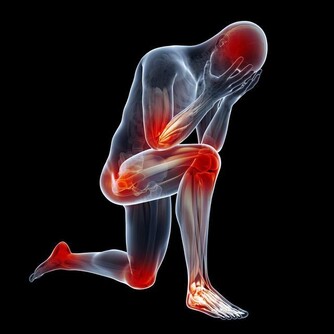

3、手掌心泛白 與常人的手掌顏色大不相同, 普通人的手掌顏色紅潤, 而患有肝病的病人手掌心泛白無血色。 4、蜘蛛痣 中間有一紅點,周圍有血絲狀, 類似於蚊蟲叮咬後的癥狀, 當用細棒一端壓迫痣中心時、全痣消失, 放開後又會出現, 這一肝病患者早期癥狀可與其他血管痣相鑑別。 據介紹,男性體表有蜘蛛痣者, 85%的人可有不同程度的肝臟組織病變, 其中約30%為肝硬化。 5、全身表現 身體乏力、容易疲勞是最常見的全身表現。 部分肝病患者可伴有不同程度黃疸, 表現為尿黃、眼睛黃和皮膚黃, 是最具有特異性的肝病癥狀(小兒生理性黃疸除外)。 黃疸過高時出現皮膚瘙癢。